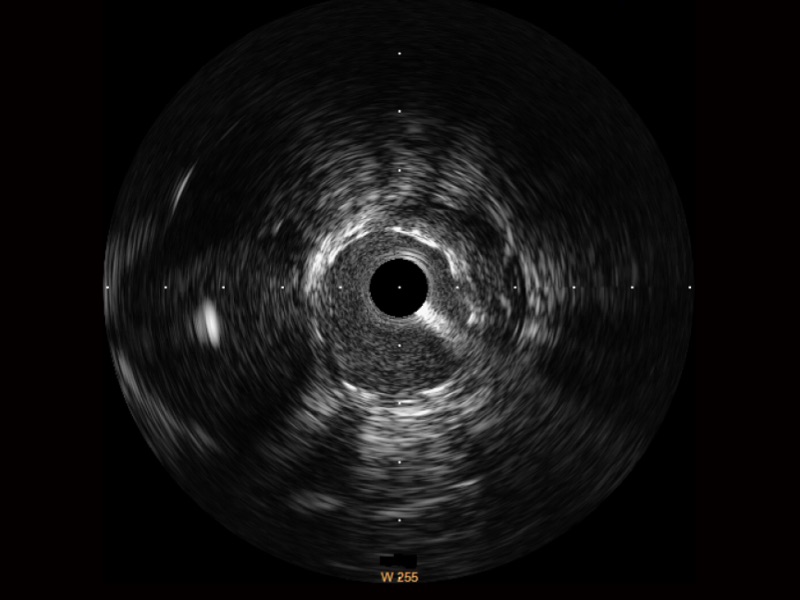

九州酷游宽频IVUS图像

对比传统IVUS导管成像,九州酷游宽频IVUS图像的近场支架梁显影更细腻,远场中膜外血管仍清晰可辨,兼顾远中近,兼顾分辨力与穿透深度